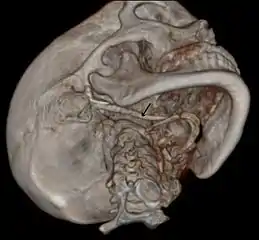

3D-reconstructed CT scan showing bilateral stylohyoid ligament ossification

3D reconstructed CT scan showing elongated styloid process (right side)

Diagnosis is suspected when a patient presents with the symptoms of the classic form of "Eagle syndrome" e.g. unilateral neck pain, sore throat or tinnitus. Sometimes the tip of the styloid process is palpable in the back of the throat. The diagnosis of the vascular type is more difficult and requires an expert opinion. One should have a high level of suspicion when neurological symptoms occur upon head rotation. Symptoms tend to be worsened on bimanual palpation of the styloid through the tonsillar bed. They may be relieved by infiltration of lidocaine into the tonsillar bed. Because of the proximity of several large vascular structures in this area this procedure should not be considered to be risk free.

Imaging is important and is diagnostic. Visualizing the styloid process on a CT scan with 3D reconstruction is the suggested imaging technique.[11] The enlarged styloid may be visible on an orthopantogram or a lateral soft tissue X ray of the neck.